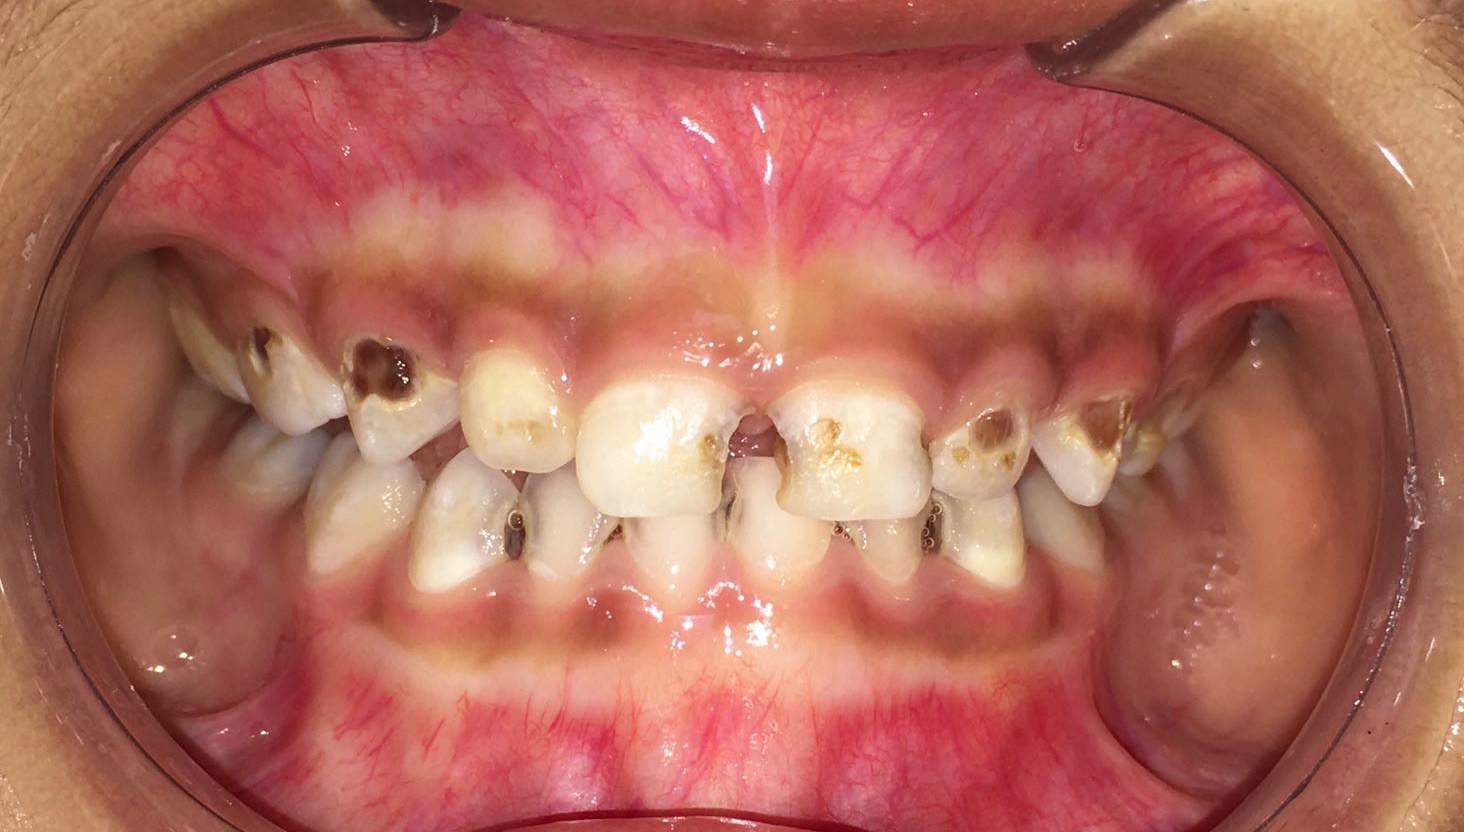

龋齿

吃糖的最大坏处就是容易导致蛀牙,糖摄入过多,加上不注意口腔卫生致使食物残渣残留,糖会被细菌分解发酵,产生酸性物质,侵蚀牙齿,使牙齿遭到破坏。预防宝宝蛀牙,糖是头号大敌。